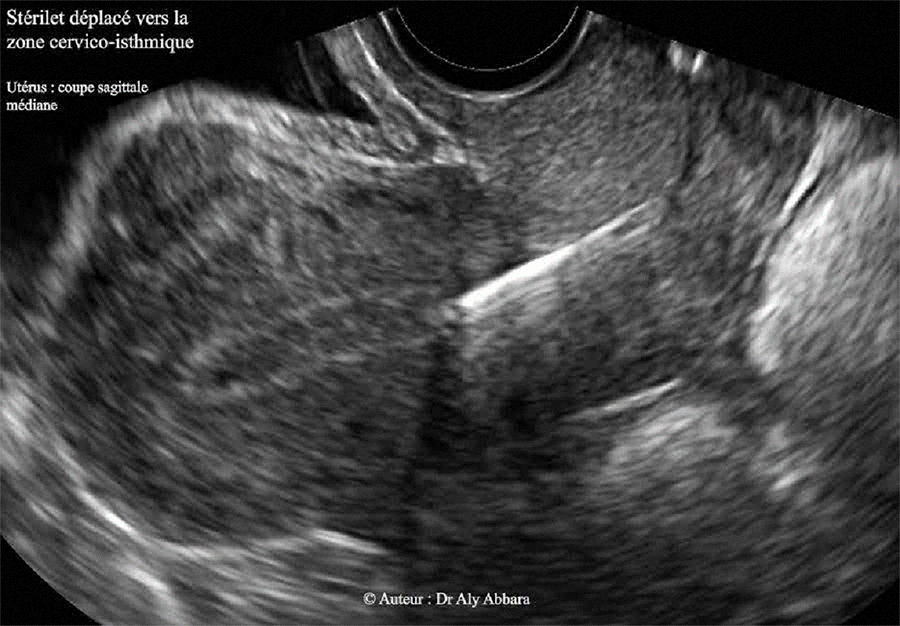

Dispositif intra-utérin (DIU) - déplacement vers la région isthmique de l'utérus

Image échographique montrant un dispositif intra-utérin (DIU- stérilet) au cuivre déplacé vers la zone cervico-isthmique de l'utérus. Ce déplacement a été mis en évidence lors d'un examen gynécologique effectué six mois après sa pose, sachant que le contrôle échographique réalisé immédiatement après la pose et 3 mois plus tard confirment la normalité de sa position dans la cavité utérine.

Ce déplacement du DIU (de type multiple-bras) est parfaitement asymptomatique ; le seul signe clinique évocateur est la longueur excessive de la portion vaginale du fil du stérilet (environ 5 cm).